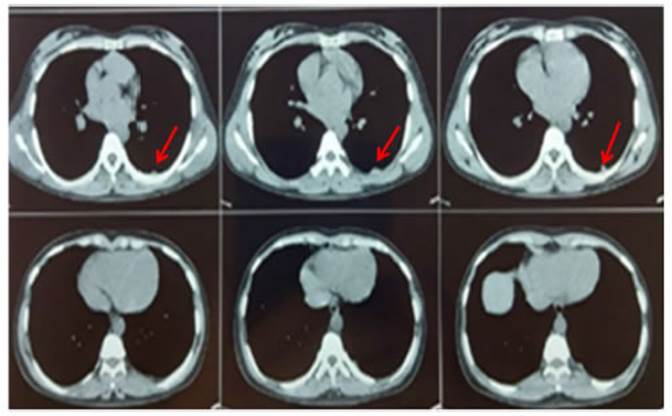

With regard to pulmonary

presentation, 54.5 % (n = 6) of the patients showed associated parenchymal

lesions: 50 % (n = 3) had solitary non-cavitary

lesions, and the rest included: 1 with solitary cavitary

lesions, 1 with bilateral non-cavitary lesions, and 1

with bilateral cavitary lesions (Figure 1).